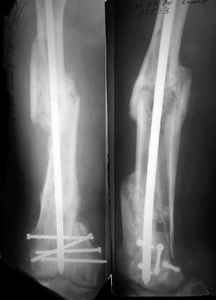

KEMMD> method of treatment for distal femur fractures

A new toy is more interesting and fashionable. And anyway it is not panacea, i have already seen presentations with LISS failures like the attached one presented by D.Seligson. And people also demonstrated incisions say that the method is not so LESS invasive as it supposed to be.